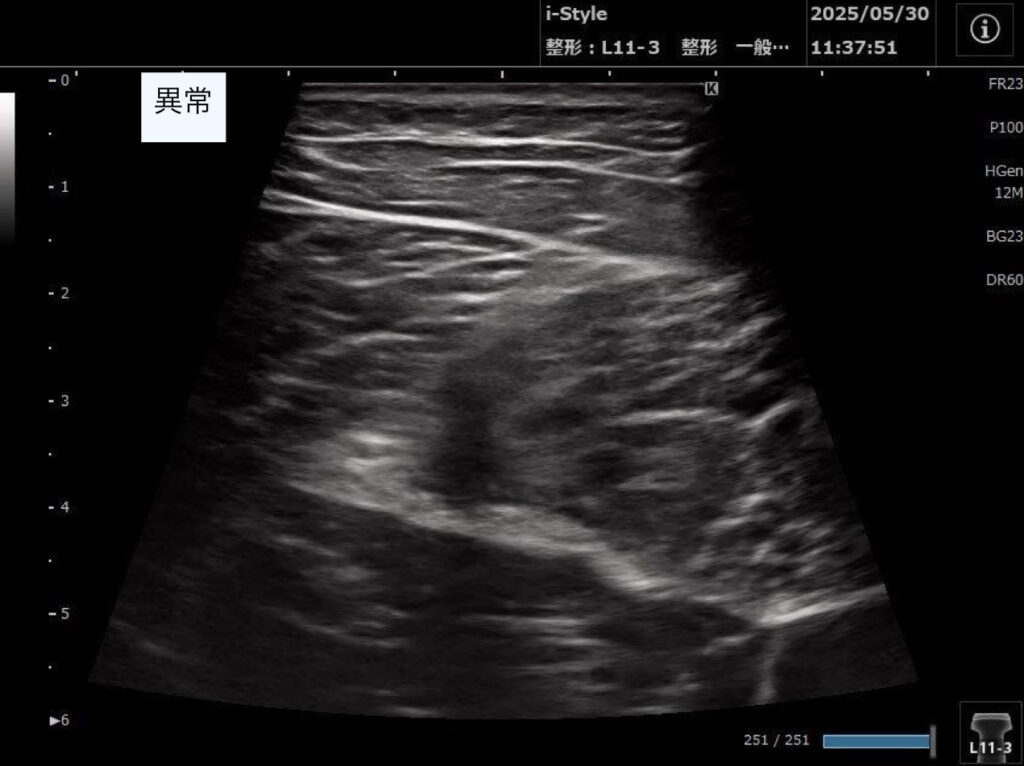

・超音波エコーで観察した結果、ハムストリングの筋が重なっている部分(共同腱)の収縮の低下があり、半腱様筋周囲に血種の低エコー像を認めた。

2回目以降:歩行や日常生活での痛みはさらに改善した。超音波エコーでの観察は毎回行い、血腫の吸収具合を確認し筋肉や神経の癒着を改善していった。

スポーツ復帰のタイミングは痛みのありなしでの判断ではなく、毎回超音波エコーで確認を行い、しっかりと筋収縮が行えることを確認できた、8週間後となった。